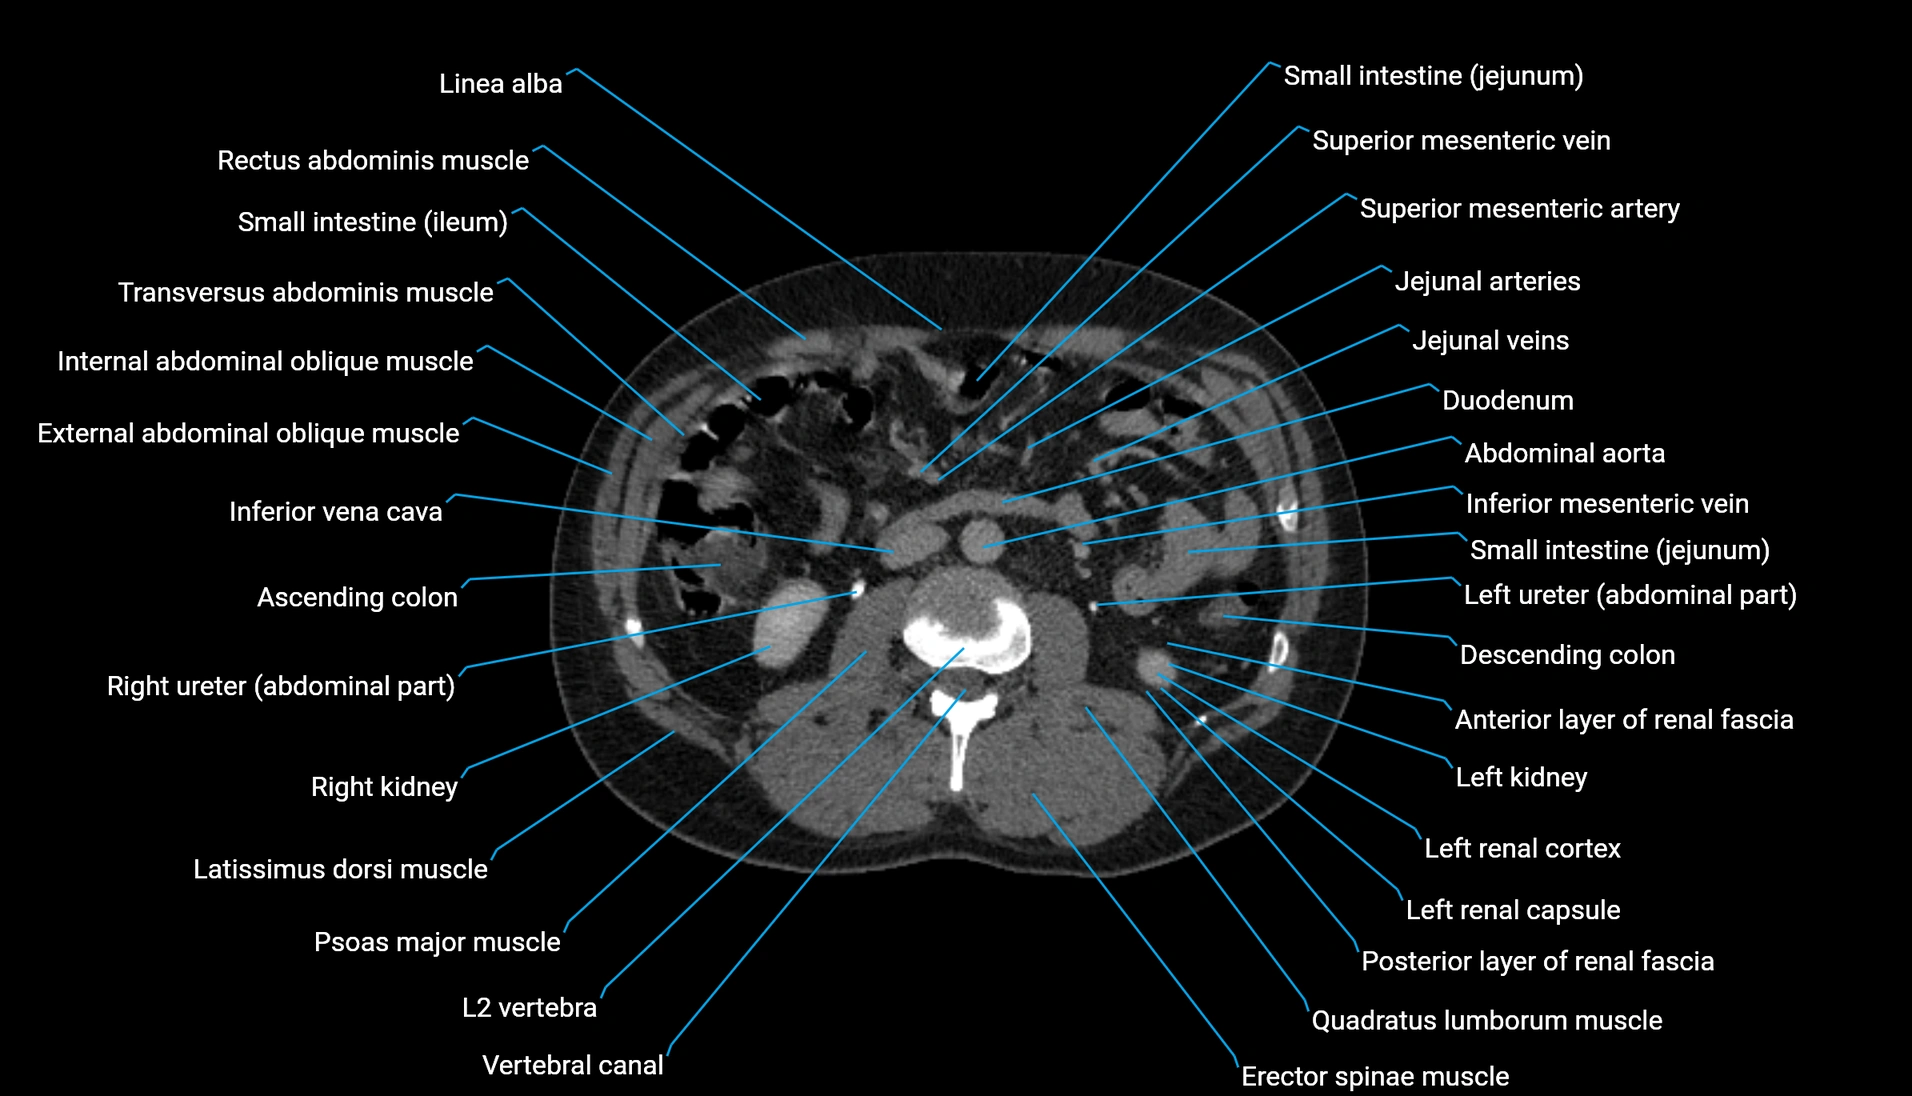

CT Appearance

Non-contrast CT:

-

Demonstrates cortical bone of acetabular rim in excellent detail

Detects fractures, dysplasia, retroversion, or bony overcoverage (pincer impingement)

3D reconstructions used in preoperative hip surgery planning

CT image